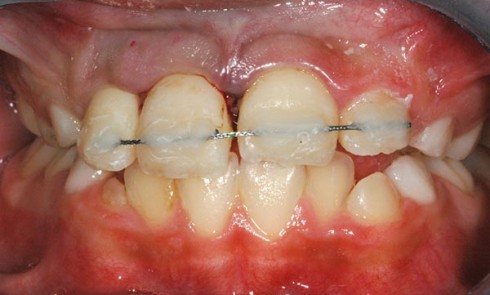

Article réservé à nos abonnés Dossier Orthodontie prothèse

Au cours des trente dernières années, les avancées dans le domaine de la recherche ont permis une meilleure connaissance des...

Article réservé à nos abonnés La demande orthodontique du patient adulte

L’une des clés de la prise en charge des adultes est « le motif de consultation ». Il existe dans...